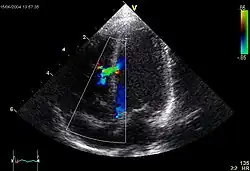

Ventricular septal defect (VSD)

Makro: Loch im Kammerseptum, meist im membranösen Teil.

Folge: Links-rechts-Shunt

![]() |